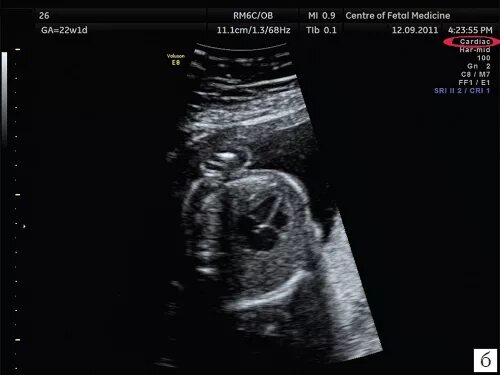

Сердце визуализация затруднена